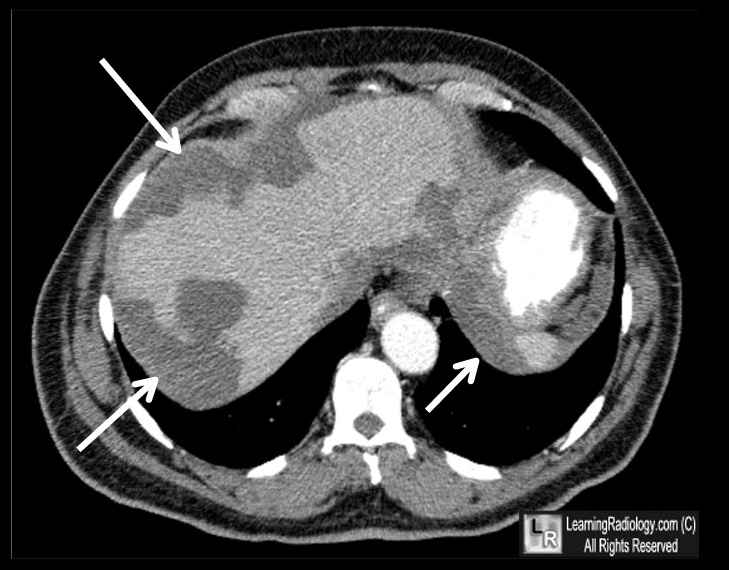

Pseudomyxoma peritonei

_Condition that is characterized by massive amounts of mucus in the peritoneum (jelly belly). It is most commonly caused by a mucinous tumor of the appendix, usually with metastasis to the ovary. (primary tumor in appendix, mucous in peritoneum, mets to ovary).,

Pseudomyxoma peritonei with massive amounts of mucus in the peritoneum (arrows)